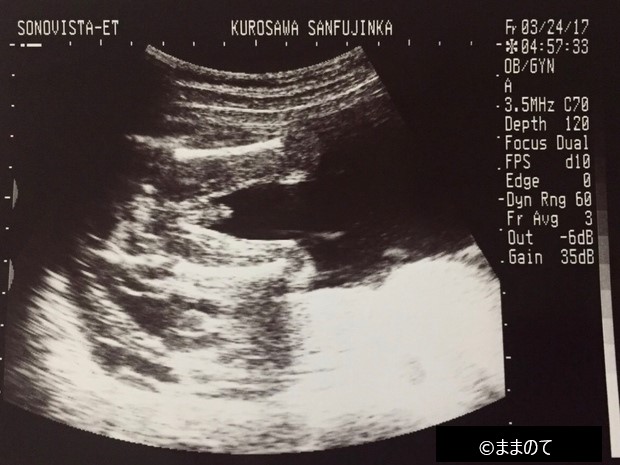

【女の子のエコー】妊娠21週

上のエコー写真は「おそらく女の子だろう」と医師が判断したときのものです。エコーの際に赤ちゃんが横向きだと、股間付近に突起物があるかないかを判断しやすいため、性別が判定しやすいといわれています。今回のエコー検査では、突起物が確認できなかったため女の子という判定がされました。